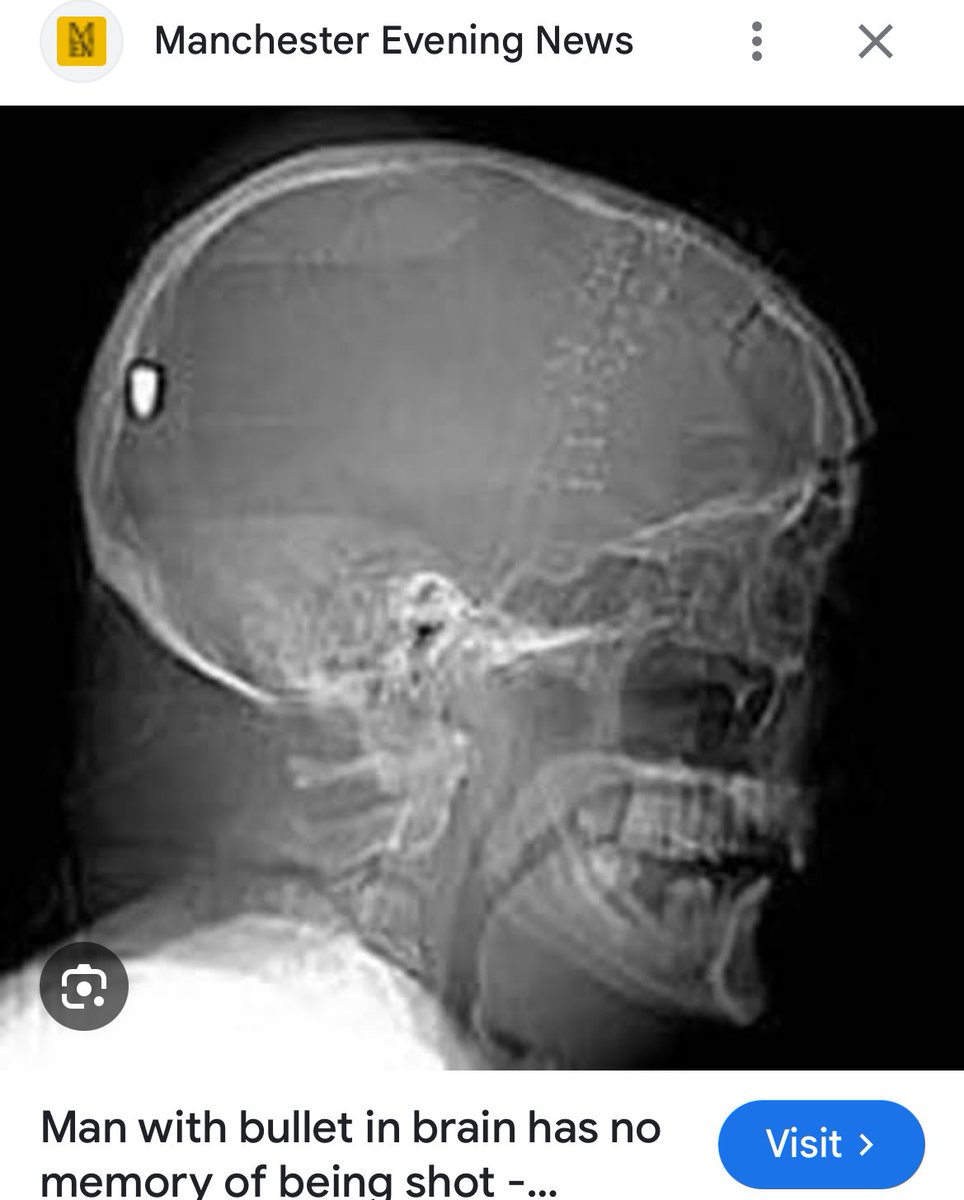

Foreign doctors in Gaza have published the X-Rays of the children that Israeli snipers deliberately shot in the head and neck with 5.56 rounds used by IDF terrorists.

The Zionists are lying about the X-Rays being fake and trying to community note this thread.

The X-Rays are real and verified by doctors and the New York Times.

Human skulls are 3 dimensional.

x-rays are 2 dimensional.

Hence. Entry and exit wounds aren’t always visible on the xray .